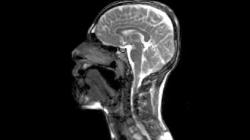

تهیه نخستین تصویر سه بعدی از حرکات زبان در زمان صحبت کردن

نخستین تصویر سه بعدی از چگونگی حرکت زبان در درون دهان در زمان حرف زدن تهیه شد.

محققان در عین حال از فناوری MRI نیز برای تصویربرداری کل سیستم گفتار انسان از جمله حنجره و نرم کام استفاده کردند.

این وب سایت دسترسی به تصاویر ویدیویی اولترسوند و MRI را فراهم می آورد که نشان دهنده حرکات دهان با سرعت واقعی و آهسته است.